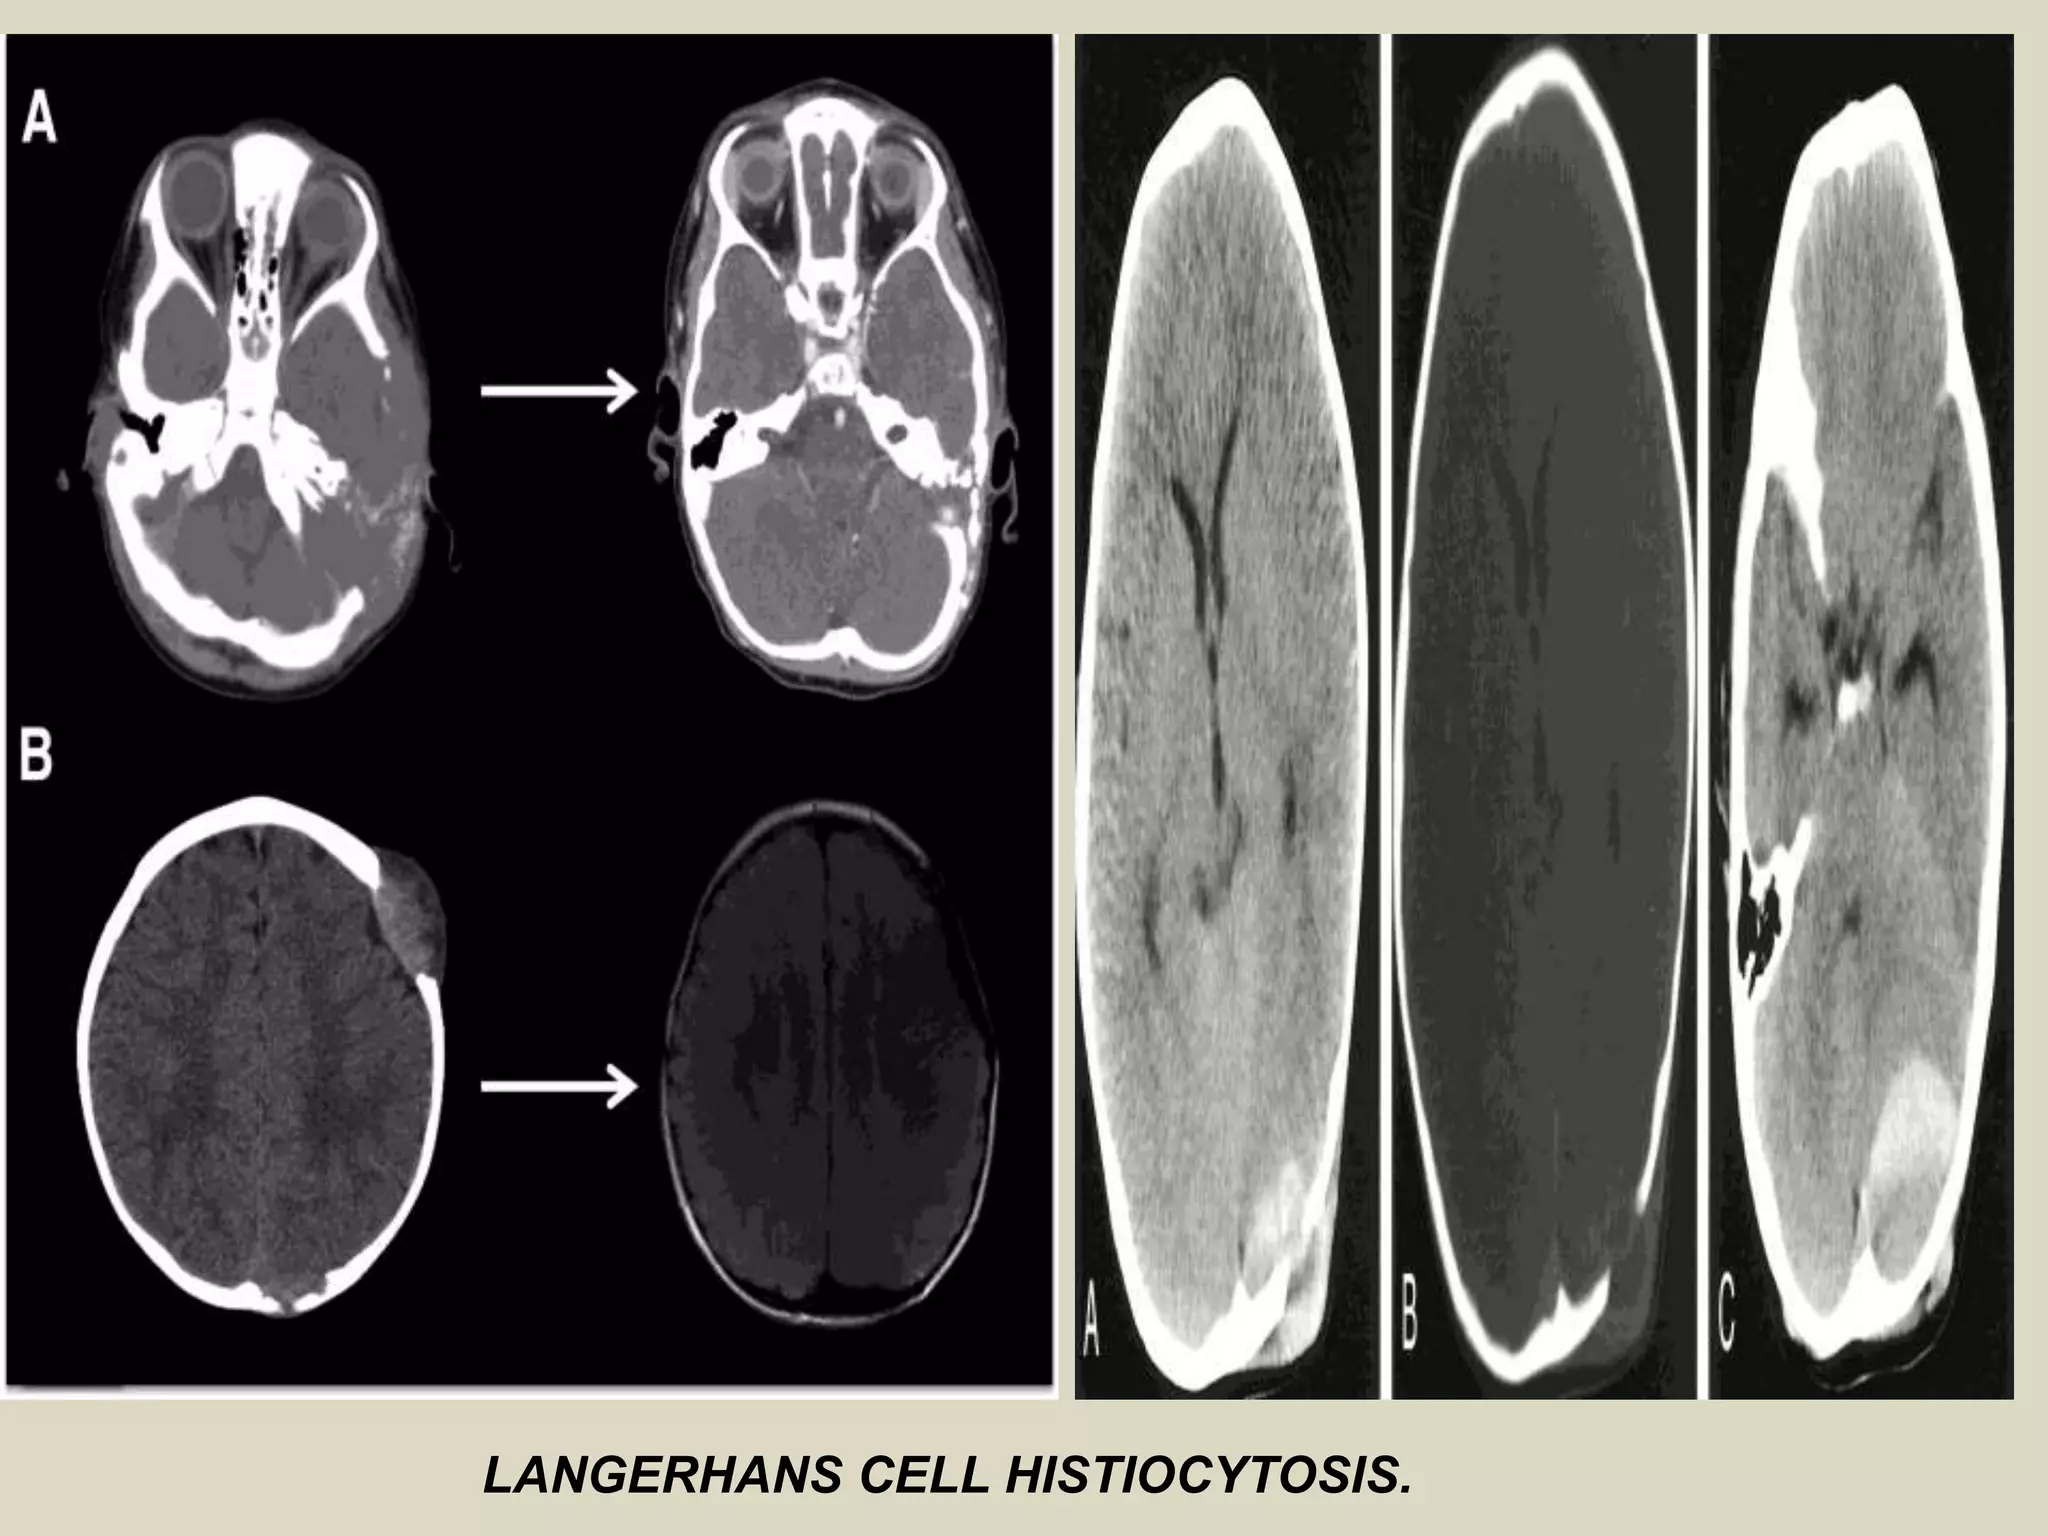

Imaging:

- LCH lesions are well defined and lytic on radiographs, however, in a minority

of cases may have ill-defined and permeative margins.

- Cortical involvement may elicit a periosteal reaction.

- Complete resolution of radiographic abnormalities may follow

treatment or occasionally occurs spontaneously.

LANGERHANS CELL HISTIOCYTOSIS .

LANGERHANS CELL HISTIOCYTOSIS.